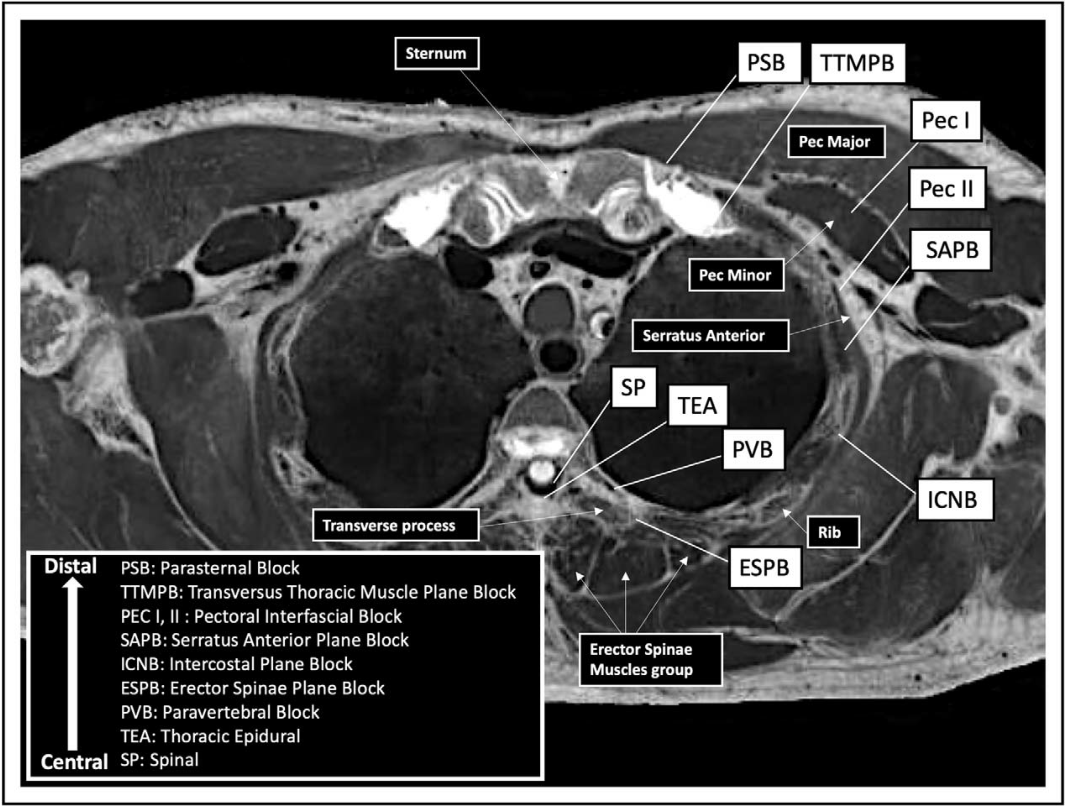

椎管内和椎旁阻滞在心脏手术中最常用,但目前对沿肋间神经路径和不同胸肌筋膜平面内进行更浅层阻滞的热情有所增加。尽管这些周围神经和筋膜间平面阻滞的风险可能较小,但其解剖位置距离椎管内间隙和胸交感神经链更远。因此,它们同时阻断躯体疼痛和交感神经反应的可能性不太(图1)。此外,因筋膜间平面内的局部麻醉剂扩散不同而躯体阻滞的程度可能不同。本综述的目的是回顾心脏手术期间的各种局部麻醉技术及其临床效果,尤其是最近18个月的新进展(表1)。

图 1.心脏手术患者使用的不同区域和椎管内阻滞从中心到远端的解剖位置。

SP:脊髓、TEA:胸段硬膜外、PVB:椎旁阻滞、ESPB:竖脊肌平面阻滞、ICNB:肋间平面阻滞、SAPB:前锯肌平面阻滞、PEC I,II:胸筋膜间阻滞、TTMPB:胸横肌平面阻滞、PSB:胸骨旁阻滞